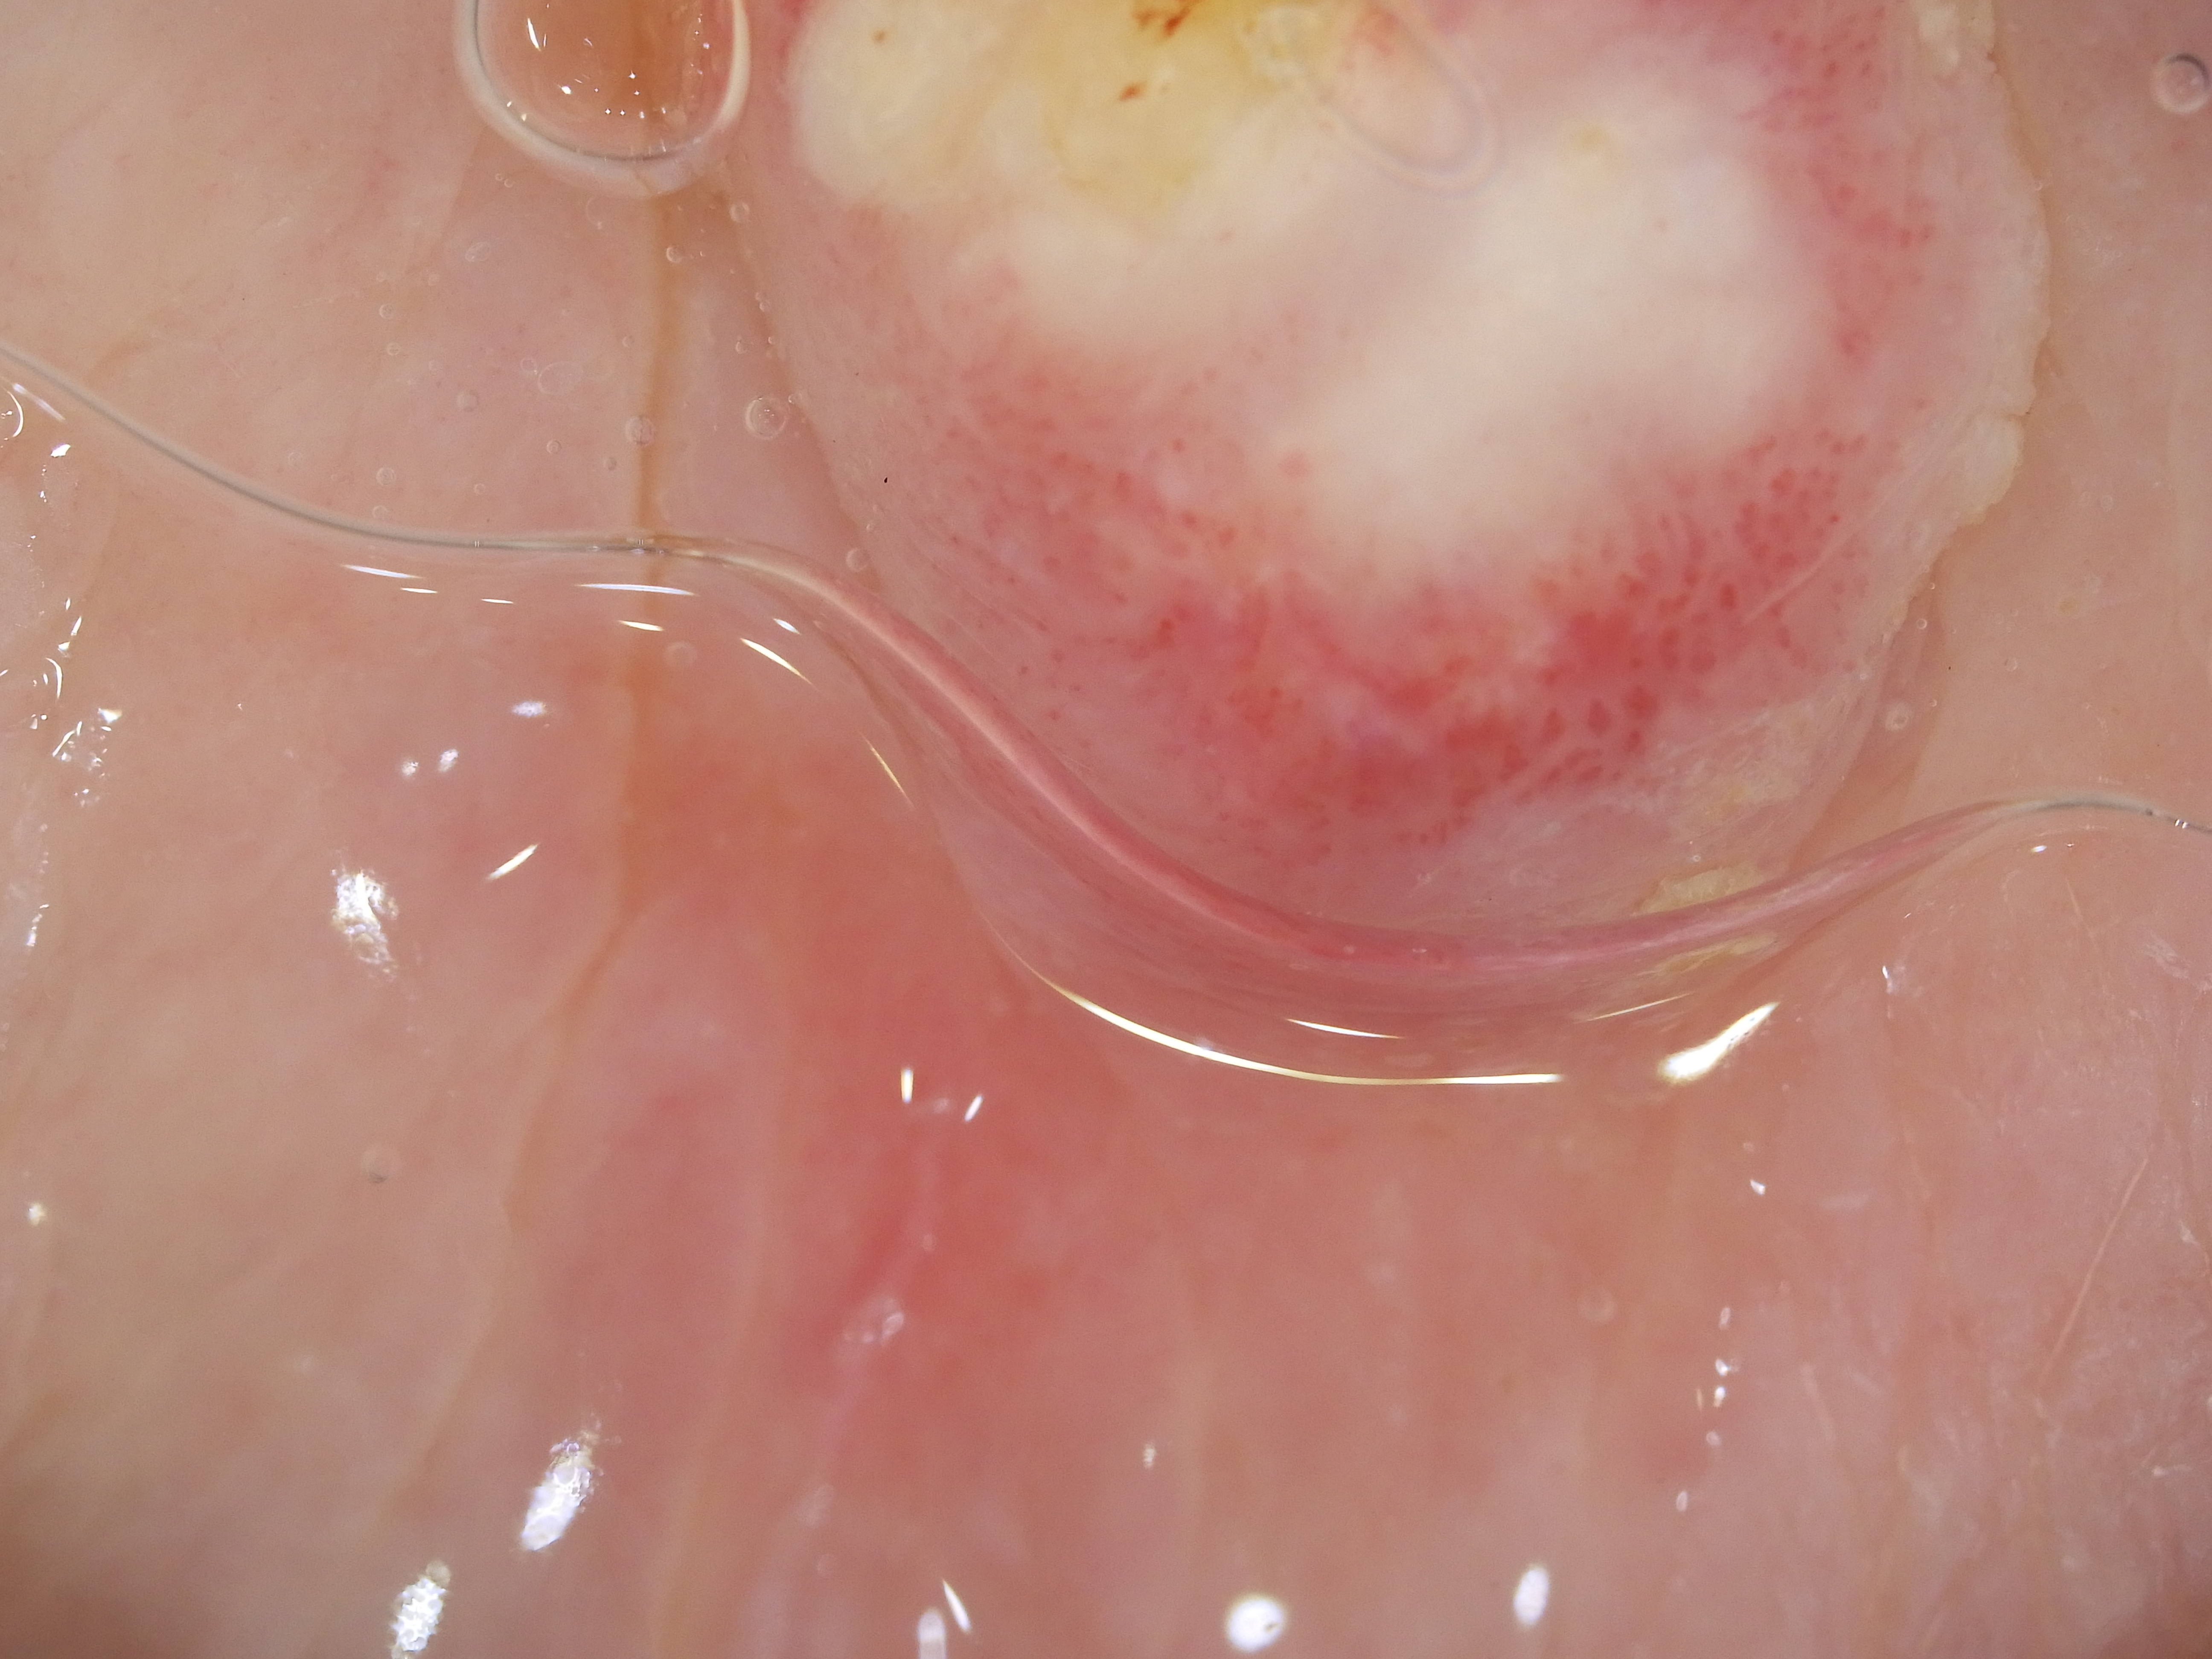

Site: Thigh

Diagnosis: Keratoacanthoma

Type: Dermlite Polarised

Description: Firm rapidly growing nodule on the thigh

This 99 years old lady developed this nodule on her thigh, It came up rapidly just after she ceaeased a Braf inhibitor drug for melanoma. It was reported as a keratoacanthoma. KAs and SCC like lesions are commonly seen in patients on Braf inhibitor drugs.

Dermatoscopy of SCCs and keratoacanthomas Dermatoscopy of solitary keratoacanthoma